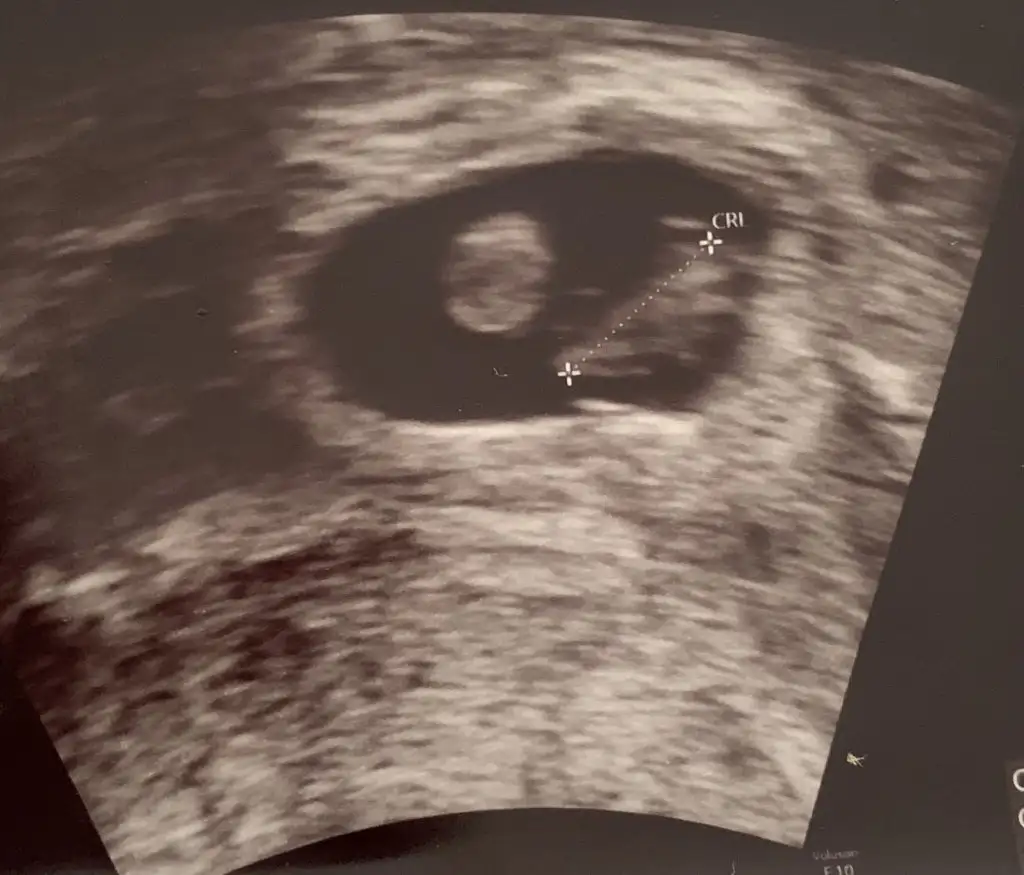

Ay tabiki efenim buyrun

Eklentiler

• 5BB76580-D737-40AE-9021-DB9FDD2BBE1C.webp

33,4 KB · Görüntüleme: 58